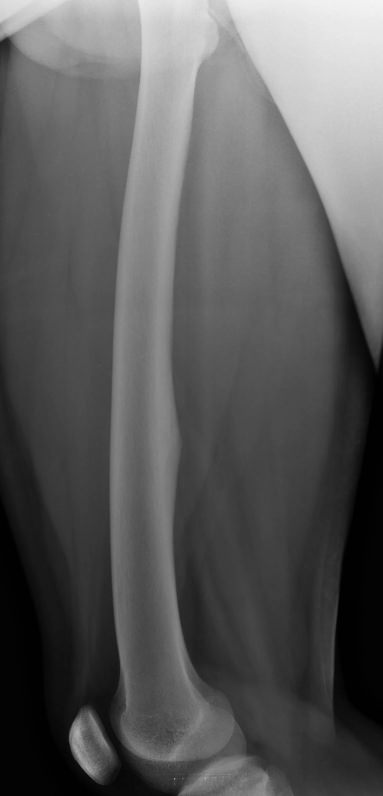

Рентгеновское исследование ― первичный вид диагностики, который назначают при переломах и подозрении на патологию костной ткани. Это неинвазивная, широко доступная и высокоинформативная процедура, во время которой пациент не испытывает никаких ощущений. Полную информацию о состоянии обследуемого участка тела можно получить уже через 10 минут после обследования. При этом современные рентгеновские аппараты излучают минимум ионизирующего излучения, позволяющие безопасно делать множество снимков в год, например, для контроля и коррекции проведенного лечения.

Что показывает рентген обеих бедренных костей в одной проекции

• Травматические повреждения одной или обеих костей ― место перелома, осколки;

• Участки изменений костной ткани, такие как воспаление, гнойное или асептическое, разрежение, размягчение, склерозирование или новообразования;

• Участки поражения мягких тканей, например, кисты, другие новообразования или миозиты, протекающие с оссификацией мышцы.